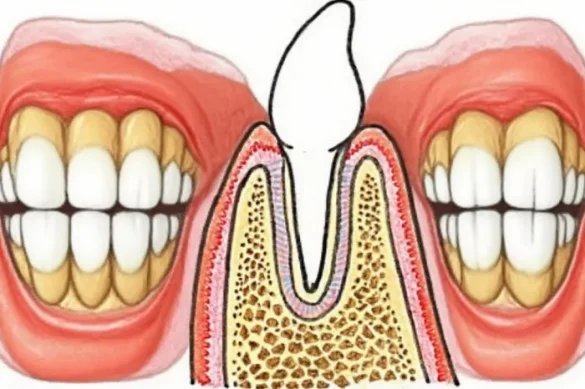

The alveolar bone, occasionally known as the alveolar technique or alveolar ridge, is the segment of the jawbone that consists of teeth sockets. This bone holds the roots of your tooth in region and presents a organization base for chewing, speaking, and preserving facial aesthetics. In humans, the alveolar bone is located in essential locations: the higher jaw (maxilla) and the decrease jaw (mandible). The curved a part of the alveolar technique bureaucracy the alveolar arch, which aligns alongside your dental arch and allows keep the right association of tooth.

On the maxilla, the alveolar bone bureaucracy a ridge on its underside, at the same time as at the mandible, it’s far a ridge alongside the pinnacle surface. The alveolar bone is blanketed via way of means of the gums and terminates at essential anatomical landmarks, consisting of the mandibular canal. Each teeth is anchored in a socket coated via way of means of a plate of dense bone called the lamina dura. Sharpey’s fibers—collagen fibers from the periodontal ligament—make bigger into the alveolar bone to assist connect tooth securely to the bone shape. Between adjoining tooth, the bone bureaucracy the interdental septum, which separates sockets and contributes to general jaw stability.

The alveolar bone is composed of:

- Outer Cortical Plate: A hard, compact layer imparting power and resistance to force.

- Inner Cortical Plate: Another compact layer going through the inner of the jaw.

- Trabecular (Cancellous) Bone: A spongy, porous principal place wealthy in blood vessels and marrow, making the bone each sturdy and lightweight.

- Alveolar Bone Proper (Bundle Bone): The bone without delay lining the teeth socket, vital for teeth attachment.

This layered shape permits the alveolar bone to soak up and distribute the forces generated via way of means of biting and chewing.